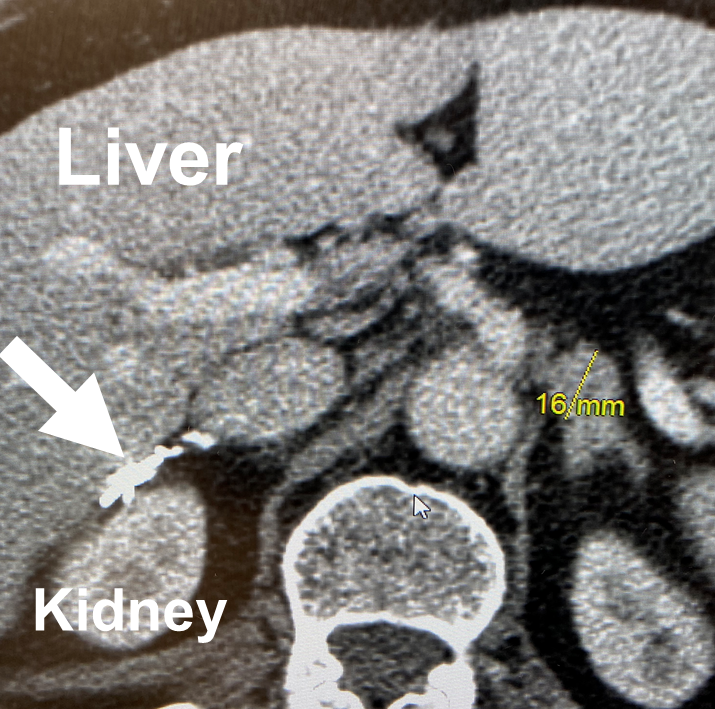

From www.researchgate.net

Nodules and calcifications observed in the adrenal gland of a patient Is Adrenal Gland Removal Dangerous You might need it if your adrenal glands make too. You have two adrenal glands in the body, one sitting. when faced with adrenal gland surgery, a few questions come to mind as to what you should know and expect before. The aim of this operation is to remove your adrenal gland. tumours found in the adrenal gland. Is Adrenal Gland Removal Dangerous.